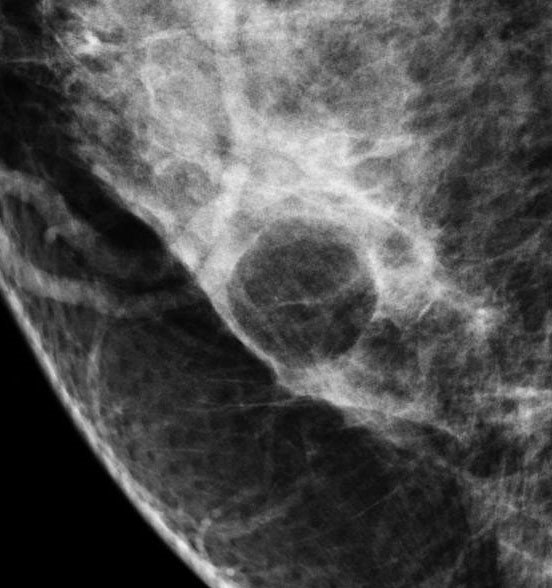

Сложные кисты обязательно подвергаются инвазивным методам диагностики с цитологическим или гистологическим исследованием материала. Вероятность озлокачествления сложной кисты равна 0.3%. При выявлениях сложных кист хирургическая тактика предлагается более активно.

сложная киста молочной железы.